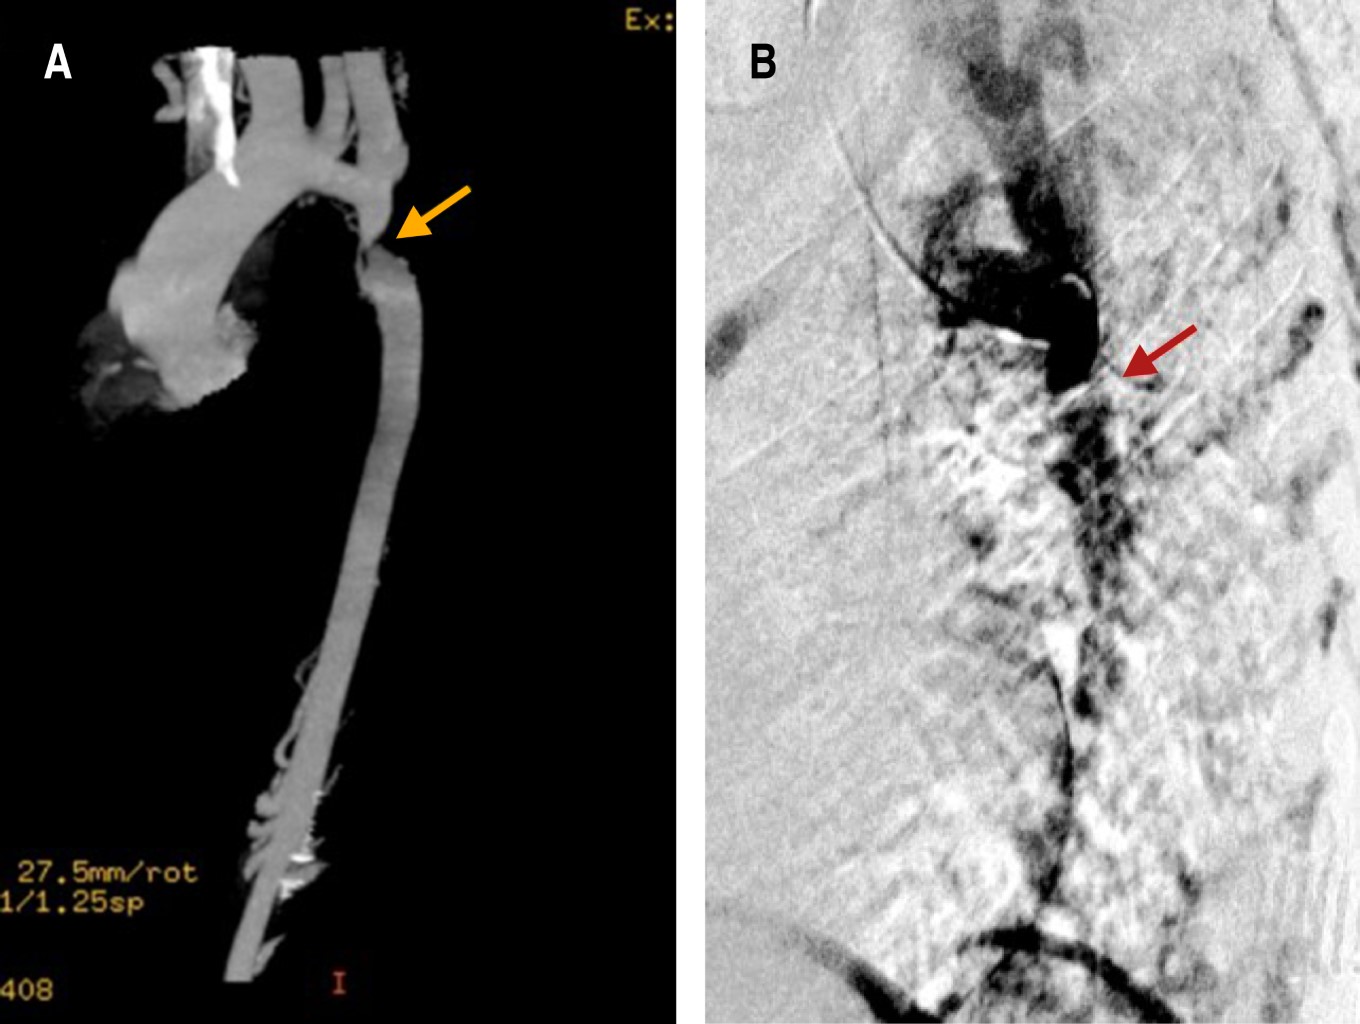

Las cardiopatías congénitas en México ocupan el segundo lugar de malformaciones congénitas en los recién nacidos, con una incidencia de 0.8-1.4%. El doble orificio de la válvula mitral (DOVM) es una cardiopatía congénita rara, con una incidencia reportada de 0.05%. Esta malformación consiste en la presentación anatómica de dos orificios mitrales comúnmente asociada a otras malformaciones congénitas como defectos septales, malformaciones completas o parciales del canal atrioventricular, coartación aórtica, tetralogía de Fallot, comunicación interauricular o interventricular, anomalía de Ebstein y persistencia del conducto arterioso. Las características clínicas son variables e incluso pueden pasar desapercibidas y ser diagnosticadas hasta la edad adulta. Se presenta el caso de una mujer joven el cual se encuentra asintomática con diagnóstico de hipertensión arterial, que durante una revisión de rutina fue diagnosticada con múltiples cardiopatías congénitas, de las cuales, su relación está poco descrita en la literatura, siendo este el tercer caso reportado. En la actualidad las técnicas de imagen multimodal permiten la mayor caracterización de las lesiones tanto de la valva como del aparato valvular, con la intención de realizar un abordaje diagnóstico y terapéutico integral para ofrecer el mayor beneficio al paciente.

Figura 1